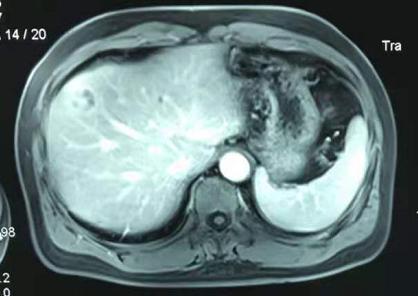

患者的核磁影像

外院的核磁提示:肝内胆管癌可能性大,肝门及腹主动脉旁淋巴结,考虑转移可能。

入院时家属的心情非常沉重,入院仔细检查后发现患者既往没有肝炎病史,肿瘤标记物均是阴性,PET-CT报告反馈非常严重,但是仔细查看核磁片子并不支持典型恶性肿瘤表现,因此术前谈话时也交代了可能存在良性疾病的可能。